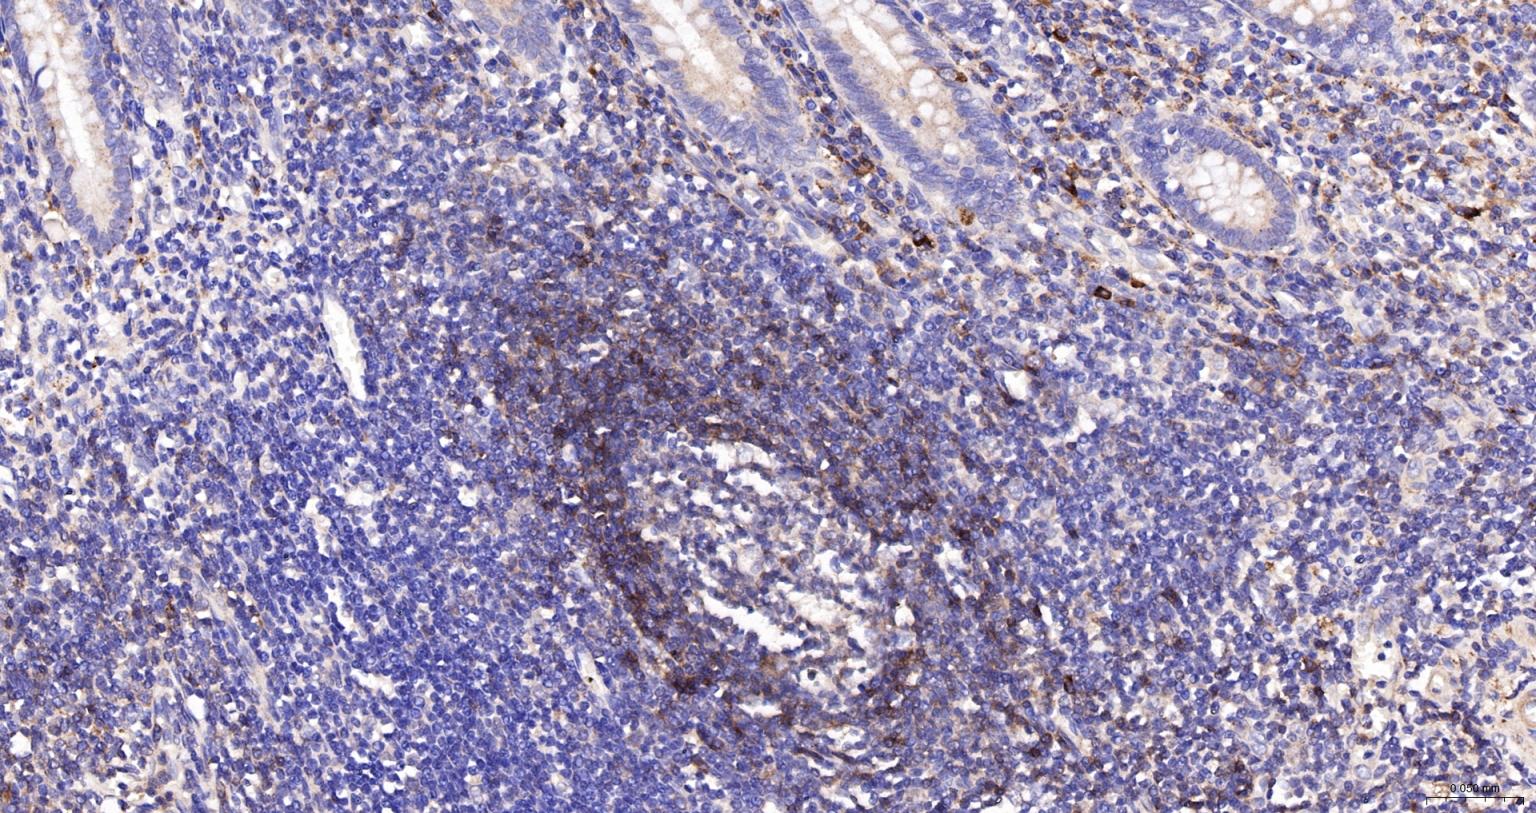

Paraformaldehyde-fixed, paraffin embedded Human appendix; Antigen retrieval by boiling in sodium citrate buffer (pH6.0) for 15 min; The section was incubated with CD79A Polyclonal Antibody, Unconjugated (bs-43765R) at 1:200 overnight at 4°C, followed by conjugation to the bs-0295G-HRP and DAB (C-0010) staining.